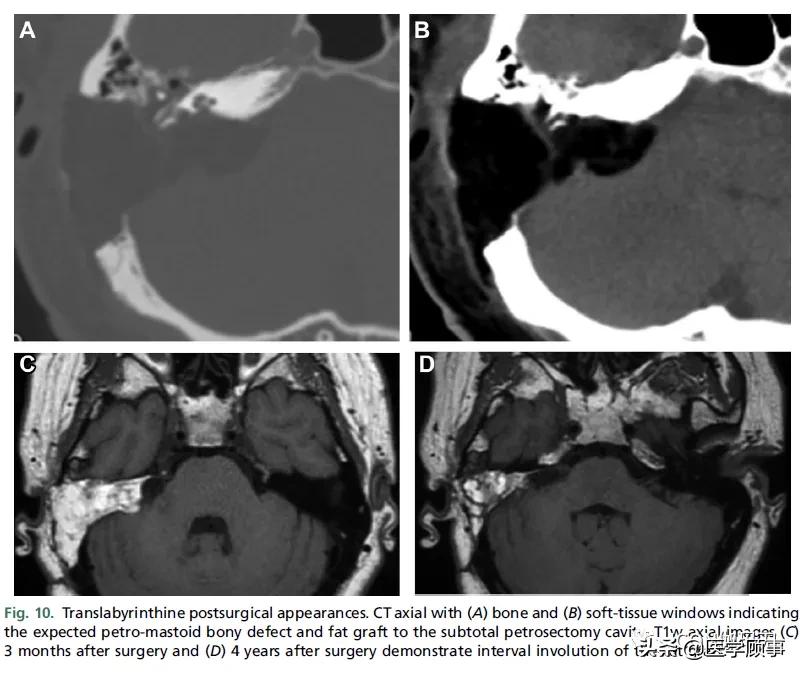

可能需要手术来解决大的或增长的桥小脑角(CPA)的前庭神经鞘瘤(VSs),主要的手术选择是乙状窦后(枕下)或迷路手术入路(图10和11)。中颅窝入路较少用于切除管内肿瘤或有小的耳道外部分的肿瘤。通过迷路和中颅窝的手术路径有保留听力的潜力。表5列出了手术步骤的总结,以及每种手术入路的优点和作用。对于年轻的患者,三叉神经痛的患者,以及有明显囊性成分的患者,手术通常优于放疗。由于放疗引起的肿瘤肿胀会导致面神经或脑干受压缺血,因此手术治疗对较大的肿瘤也有好处。

图10。经迷路手术后的表现。CT轴位显示(A)骨和(B)软组织窗,表明预期的岩骨乳突骨缺损和脂肪移植到次全岩骨切除术腔。T1w轴位图像(C)术后3个月和(D)术后4年显示脂肪移植物的间隔退化。